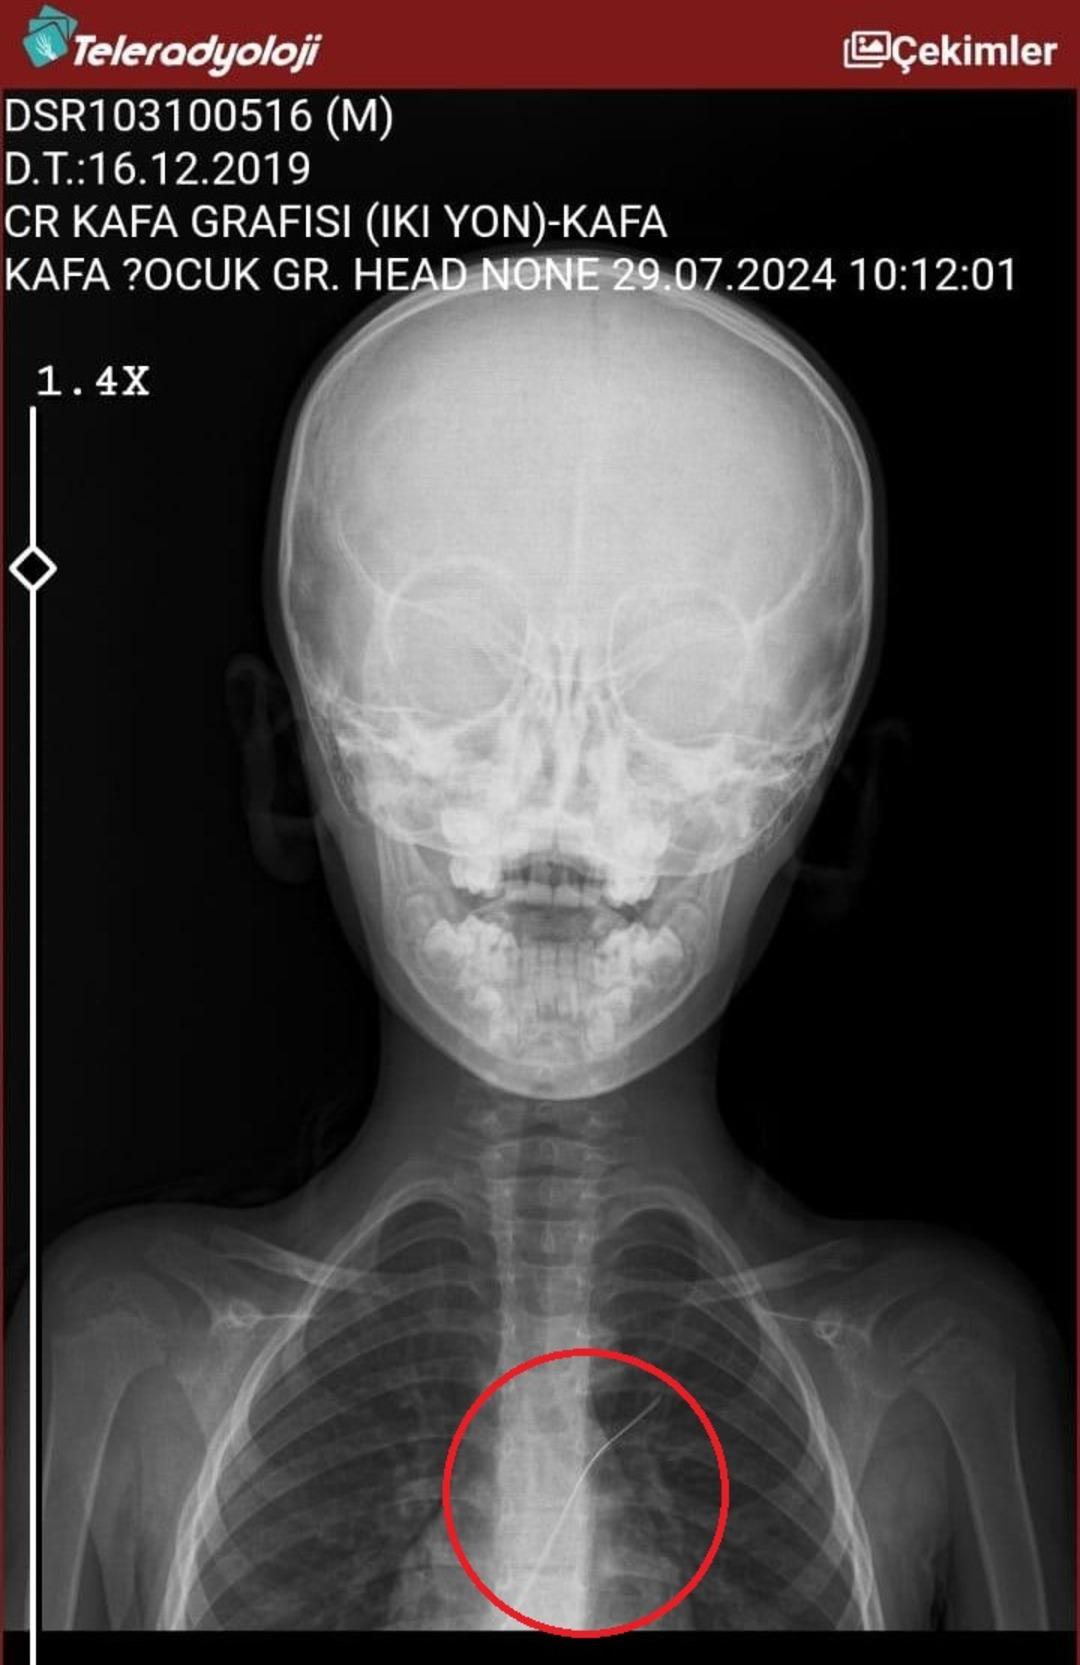

Seamore (37) ve Şaç'ta yaşayan Mehmet Ötün (40), Mayıs ayında bir parça salatalık yuttuktan sonra öksürük ve kusma şikayetleri gözlendiğinde Sernak Eyalet Hastanesine getirildi. Burada, ARAM gövdesinde yarıçap X ve manyetik rezonans görüntüleme unutuldu. Diyarbakir Gazi Yeşargil'in eğitim ve araştırma hastanesi jinekolojiye ve ARAM'lar için ek binaya yönlendirildi, 18 santimetrede 5.5 saatlik riskli cerrahi kaldırıldı. Postoperatif araştırmalarda, kateter kalp kapakına ve karaciğere zarar vermeye kararlıydı.

Aile avukatı Ahmet Yalçın, ikisinin de hastaneden şikayet ettiklerini ve bir dava açtıklarını açıkladı ve şunları söyledi: “Müvekkilim Eylül 2022'de Stevens -Johnson'un kariyeri nedeniyle Eylül 2022'de Dicole'deki üniversite hastanesinde tedavi edildi. Kateter ona saldırıya uğradı.